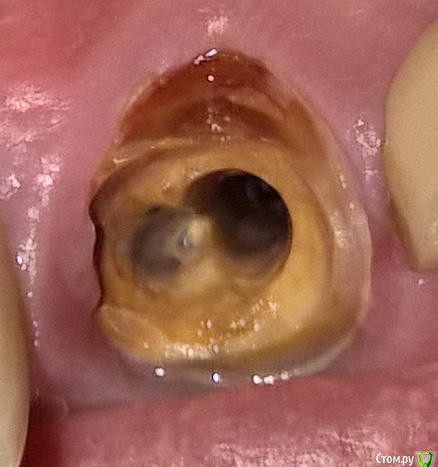

vova_nike Опубликовано 25 декабря, 2015 Поделиться Опубликовано 25 декабря, 2015 На верхнем переднем зубе, стояла с 2003 года, расцементировалась 1-й раз в янв. 2009, доктор вклеил ту же вкладку и новую коронку. Начала шататься на уровне ощущений примерно 3 мес назад, неделю назад я ей окончательно помог.Клиника моя закрылась, контактов нет. Пошел почти в ближайшую частную стоматологию, в надежде вклеить и, возможно, установить мост мк на 4 передних, они все под керамикой. Но доктор сказал удалять и имплантировать. смущает это пятно цвета йода, у меня был перелом челюсти в 2012 и похоже этот кариес начался тогда, от шинирующей проволоки. Я понимаю, что имплантация - это (наверное) идеальный вариант, а нет ли возможности (и есть ли смысл) сохранить корень и отсрочить эту процедуру на более-менее приличное время? Снимка нет, доктор сказал идти делать КТ 3D Ссылка на комментарий